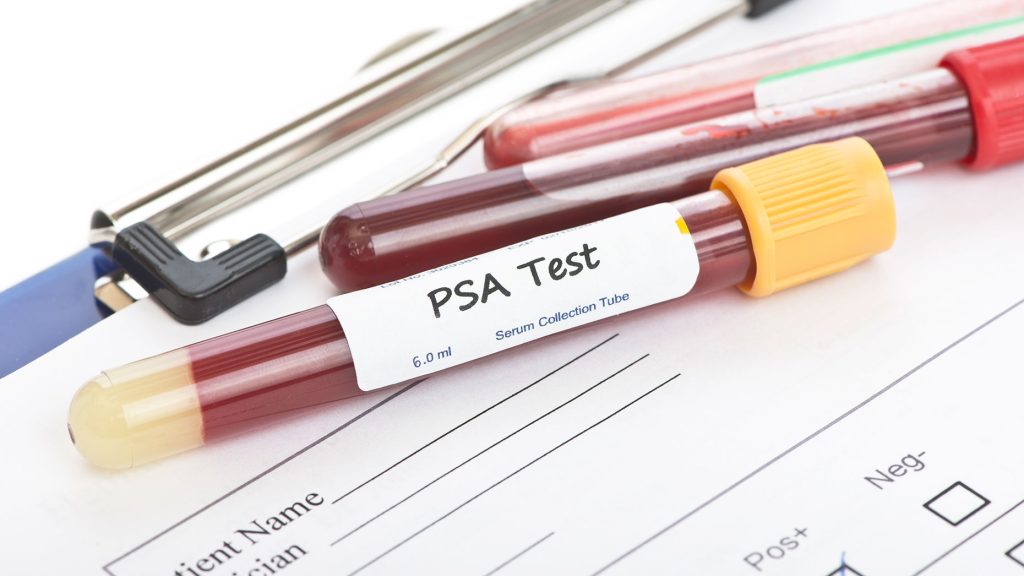

Καρκίνος

PRONEWS.GR / Υγεία